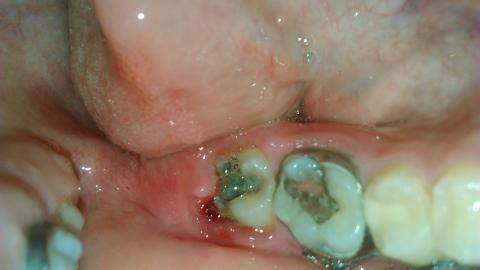

sisuska - 26.5.2015 6:22:02 Dobry den,prosím vas o radu. Vcera som cítila taky zvlastny pocit okolo osmicky, no rano som sa zobudila na to,ze ma to boli a mam to opuchnuté,červené. Mam 16 rokov,na zuboch nosim uz par rokov strojcek, kedze som ich mala dost krive.vzhladom na to,neviem,ci mam dostatočnu dentalnu hygienu.vlozila som aj foto a za akukolvek odpoved budem vdacna,pokym nebude možné navštíviť svojho zubara.myslite,ze je to zapal?

Dobrý den, tohle nevypadá na zánět, ale jde o prořezávání osmičky. Bohužel se toto stává, osmičky rostou dlouho a tyto problémy se mohou vyskytovat. Můžete zkusit lokální dezinfekční prostředky typu Tamtum verše, nebo navštívit zubaře, který dáseň mírně nařízne a uvolní tak tlak rostoucího zubu na ni.